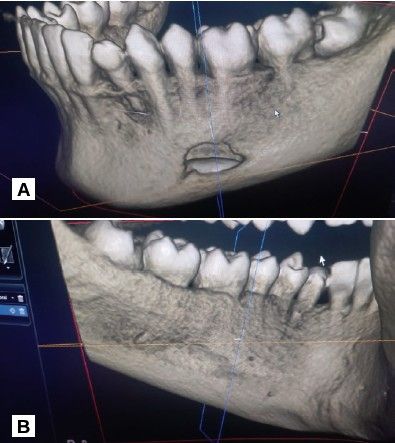

Los cortes ortorradiales ofrecieron información sobre la ausencia de expansión de corticales, conservación de la cortical lingual y a la altura del segundo premolar ligera perforación de la cortical vestibular (Figuras 3A y 3B). Las reconstrucciones 3D corroboraron los hallazgos anteriormente descritos (Figuras 4A y 4B).